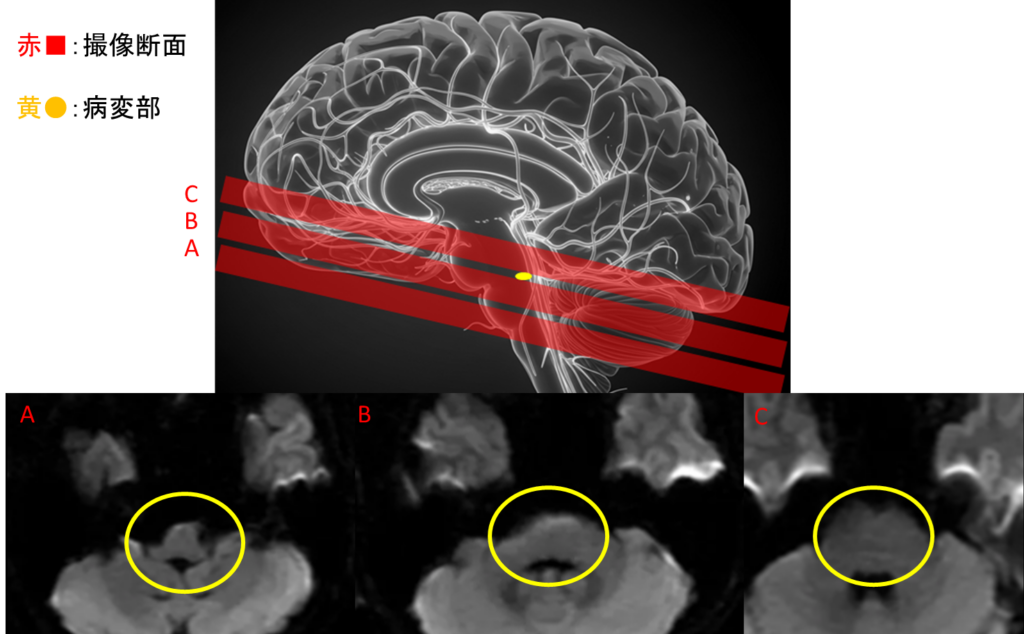

通常の頭部MRIにおけるDWI(脳梗塞を映し出す画像)では異常所見は見当たらない。(黄〇内に異常を示す高信号(白く光る)は指摘できない)

ABCは5mmずつ脳を撮影し、1mmの間隔を開けて撮っている。

異常所見となる”黄色点”が埋もれてしまう、または隙間に入ってしまう事がある。

脳幹部用に、3mmで細かく隙間なく追加検査すると異常所見となる梗塞(黄色➡)が高信号として描出できた。

また、脳幹を様々な角度で同様に撮ることで病変を確実にとらえることが出来た。